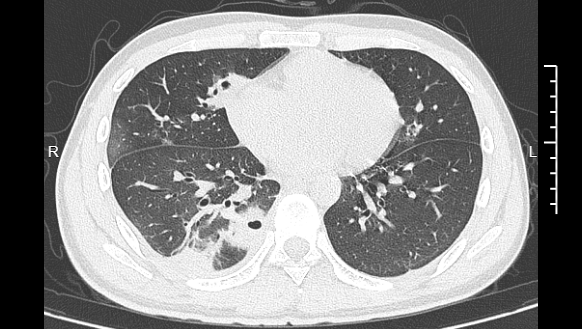

熬到第三天,小林体温升至39℃,赶紧就医。接诊的丁群力主任医师根据症状,立即安排CT检查。结果显示:小林肺部有十几个空洞,部分肺组织已坏死,属于典型的血源性肺脓肿。

▲小林的CT影像显示肺部存在多个空洞